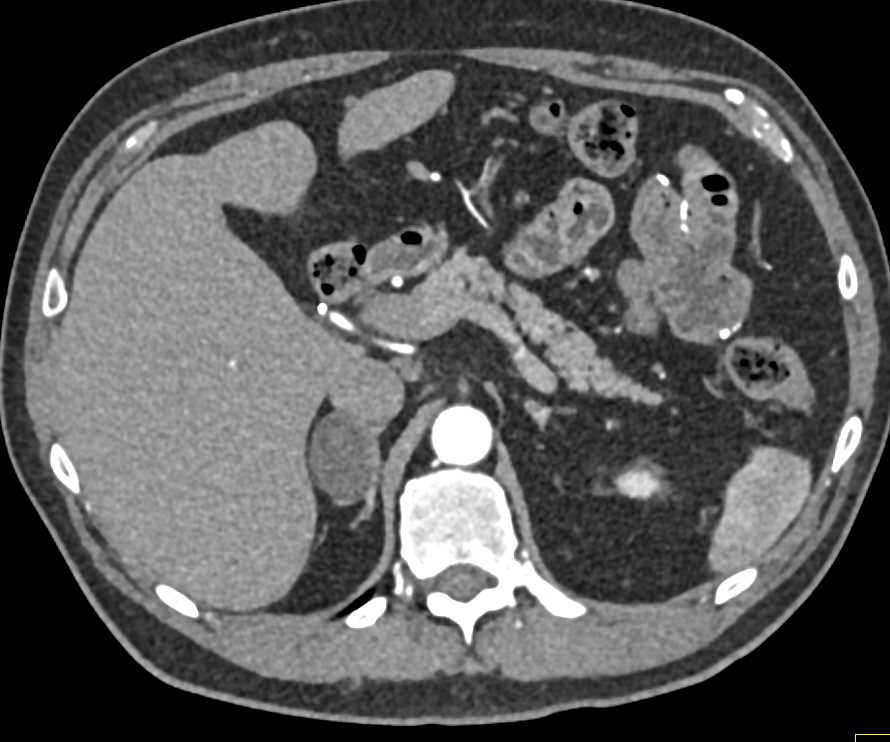

Pheochromocytoma Left Adrenal Gland